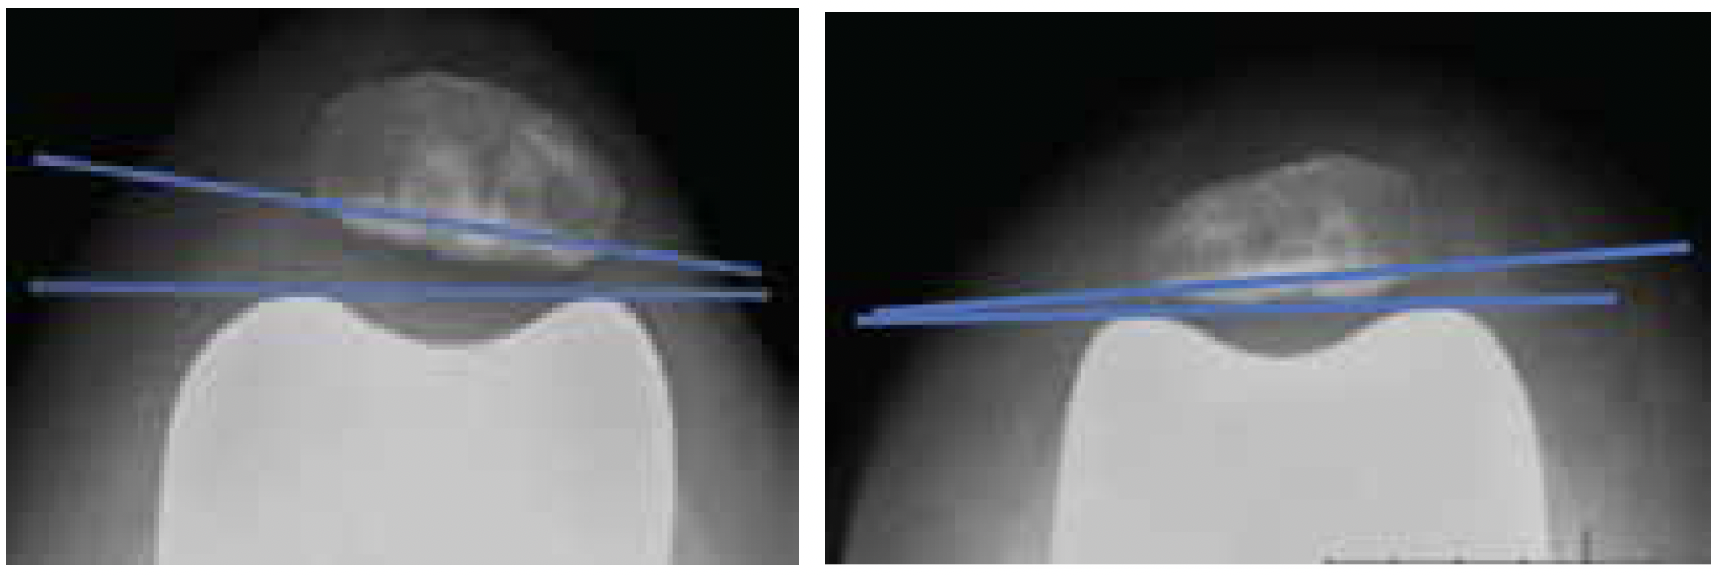

IMPROVED PATELLA TRACKING / LESS PATELLA TILT

Patellar tilt comparison: asymmetrical (left) vs. symmetrical (right) femurs